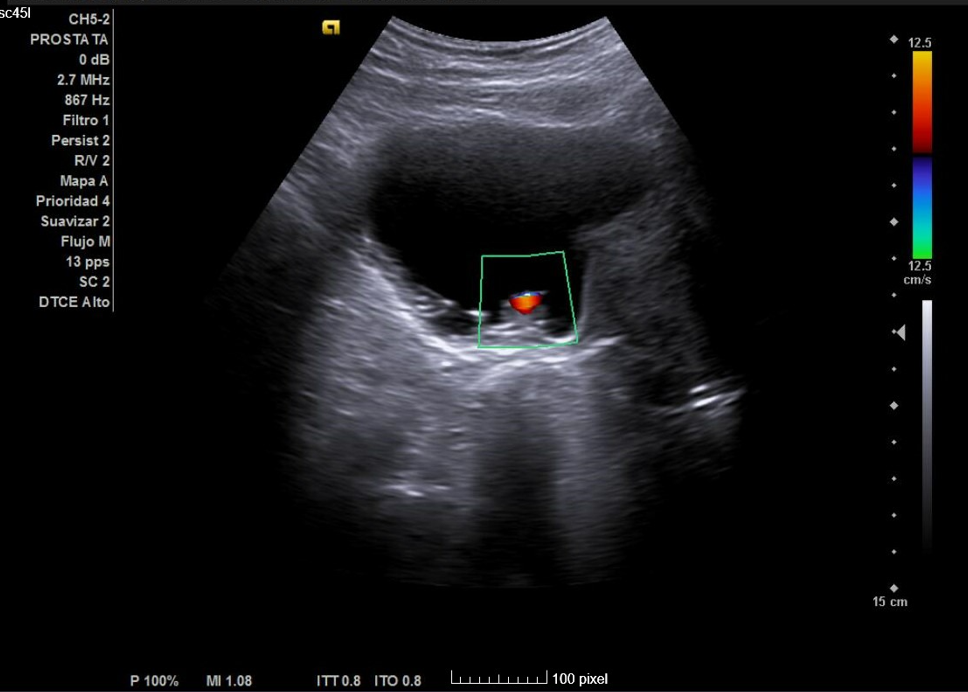

Primera ecografía: Riñón derecho de 9,6 cm, izquierdo de 9,5 cm, escoestructura y morfología normales. Vejiga con aumento de grosor de pared, residuo premiccional y posmiccional similares en torno a 350 cc (probable vejiga de lucha). Pólipo vesical a expensas de pared inferior izquierda de 18,5 x 8,7 mm. Jet ureteral bilateral conservado. Próstata de 110 cc. Se repite ecografía al mes: Pólipo vesical de 14 x 9,7 mm, próstata de 119 cc, vejiga con volumen premiccional 469 ml y posmiccional 400 ml.

• Se comprueba hipertrofia prostática; además, se observa pólipo vesical de etiología no filiada (a descartar neoplasia vesical).